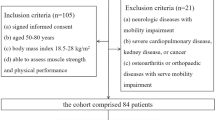

The study was conducted prospectively as a case–control study. It was approved by the local research ethics committee and all participants provided written informed consent. Recruitment began in May 2017 and ended in July 2018. Myositis patients were recruited from the outpatient rheumatology clinics and inpatient wards at Leeds Teaching Hospitals Trust. Sex and age frequency-matched healthy controls (matching the number of patients within categories defined by sex and 5-year age bands) were recruited from the University of Leeds and the Leeds Teaching Hospitals Trust and via advertisements on social media. No formal sample size/power calculations were carried out owing to a lack of available data. However, to estimate parameters for powering future clinical trials, published rules of thumb recommend between 12 and 30 subjects per group of interest [18, 19].

Inclusion/exclusion criteria

For IIM patients, we recruited adult patients with an established diagnosis of adult IIM according to previously described criteria [20, 21]. Additionally, we only included patients with active disease who presented demonstrable muscle weakness (determined subjectively by a qualified physician or quantitively by a manual muscle test–8 score < 125/150) and at least two abnormal measures from the following:

Patients were excluded if they had a history of spinal disease or neuropathy, or any contraindication to MRI. For healthy controls, we recruited asymptomatic adults (aged > 18 years) with no previous history of muscle disorders, arthritis or neuropathy. None of the participants was currently on HMG-CoA reductase inhibitors (statins).

Patients and characteristics

A total of 23 patients diagnosed with IIM volunteered to participate in this study (10 males and 13 females; mean age [SD] = 50.4 years [16.1]). Clinical data of the recruited IIM patients are listed in Table 1. With regard to disease activity, 4 patients had a normal level of CK, but re-presented with significant muscle weakness and were determined as clinically active by the physician. The patients were frequency-matched to 23 healthy controls. The descriptive characteristics of the patients and healthy controls are represented and tested for differences in Table 2. Five IIM patients failed to perform the ETGUG test, of 2 of whom also failed to perform the knee extension/flexion due to severe muscle weakness.